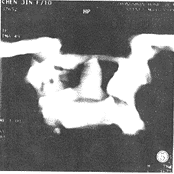

寰樞關節脫位這些患者並沒有經受很大的暴力傷,有些甚至沒有外傷史,只是因為頸痛就診攝了開口位X線片,見到齒狀突與兩側寰椎側塊不等距。有些病例CT橫截面上也見到兩側寰齒側間隙不等距。這些病例都經過了牽引及支具治療,均未能糾正“脫位”,個別病例甚至因此而做了寰樞關節融合術。對這些病例作出“寰樞關節脫位”的診斷是不恰當的。如果有齒狀突骨折,在頸椎側位片及開口位片上可以見到骨折線或骨折移位的影像。橫截面的CT可以觀察到寰椎橫韌帶的起止點是否有撕脫骨折。如果橫截面CT影像見寰樞關節鏇轉角度超過47度,即可診斷寰樞關節脫位。

寰樞關節脫位2、CT檢查:

可與寰椎椎弓骨折及上頸椎畸形等疾病相鑑別,特別在頸部有創傷史,有頸部疼痛,僵硬或固定體位。而x線未發現異常時,CT檢查有助於防止漏診。